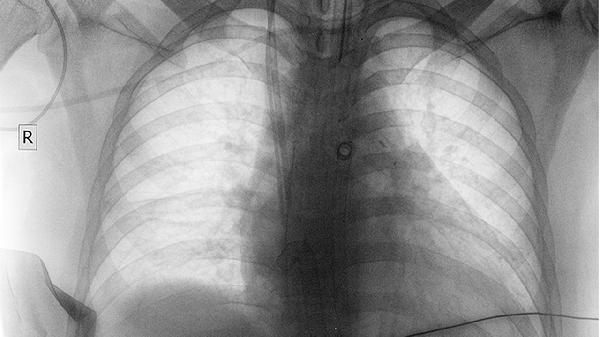

建议患者在用药期间定期复查影像学与基因检测,根据疗效及时调整方案。配合均衡饮食与适度运动可改善机体耐受性,避免食用西柚等影响药物代谢的食物。若出现严重皮疹或间质性肺炎等不良反应应立即就医。